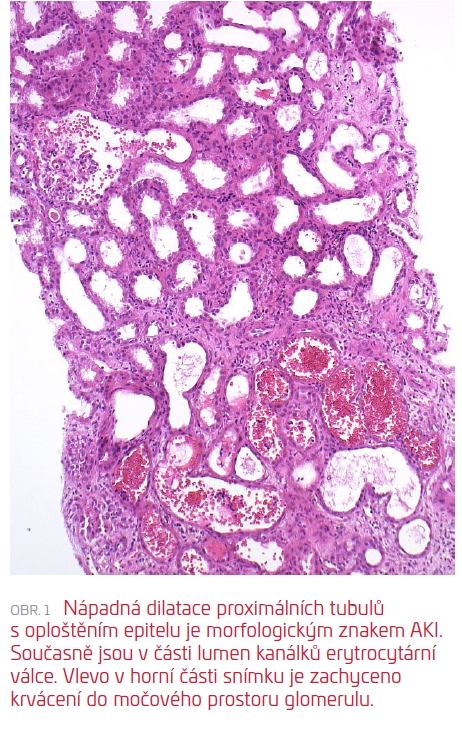

Následně (17. den od přijetí) byla provedena RB, která zachytila těsně subkapsulární punktát s morfologií akutní tubulární nekrózy s četnými čerstvými i lyzovanými erytrocyty/erytrocytárními válci v lumen tubulů, velmi pravděpodobně odpovídající antikoagulancii indukované nefropatii (viz obr. 1 a obr. 2). Současně byla diagnostikována glomerulonefritida s monoklonálními depozity (IgG, IgG3, C3 pozitivní), velmi suspektně jako součást prokázaného hematologického onemocnění (B‑NHL mantle cell lymfom). V subkapsulárním punktátu bez punkce arterií nebylo možné posoudit stav cév a rozsah spolupodílu vaskulární nefrosklerózy, který může limitovat další úpravu renálních funkcí.